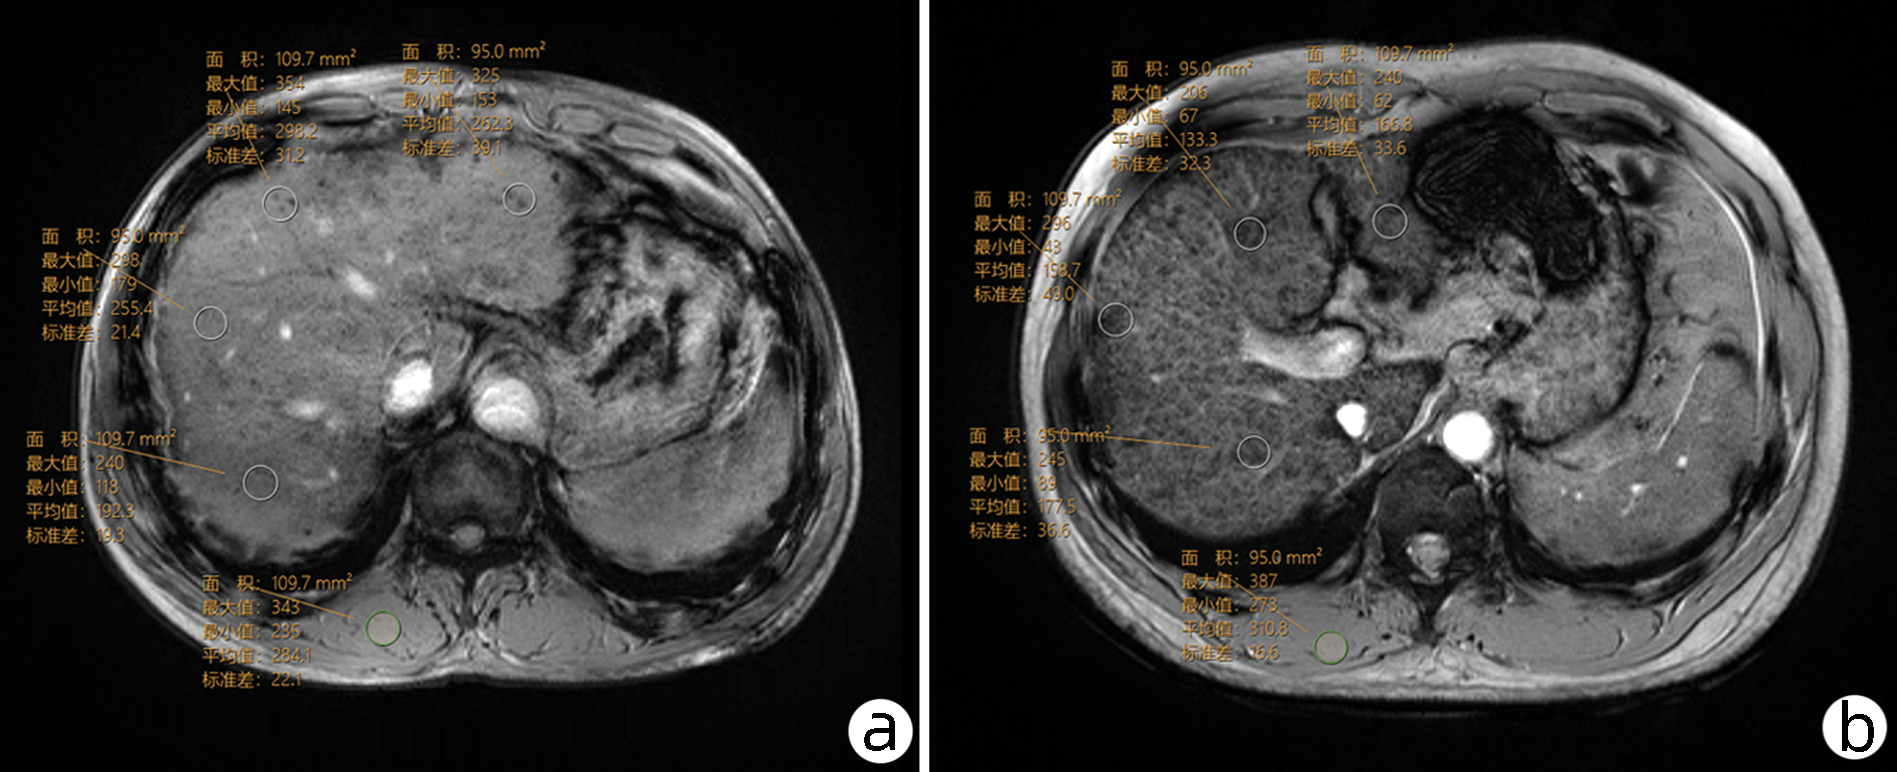

Massive hepatic hemangioma with diffuse arterioportal fistula: A case report

Bangjian ZHOU, Jun YANG, Yu YIN, Xiaoli ZHU, Caifang NI, Wansheng WANG

2023, 39(3): 640-643. DOI: 10.3969/j.issn.1001-5256.2023.03.025

Abstract(977) HTML (223) PDF (3500KB)(99)

Abstract: